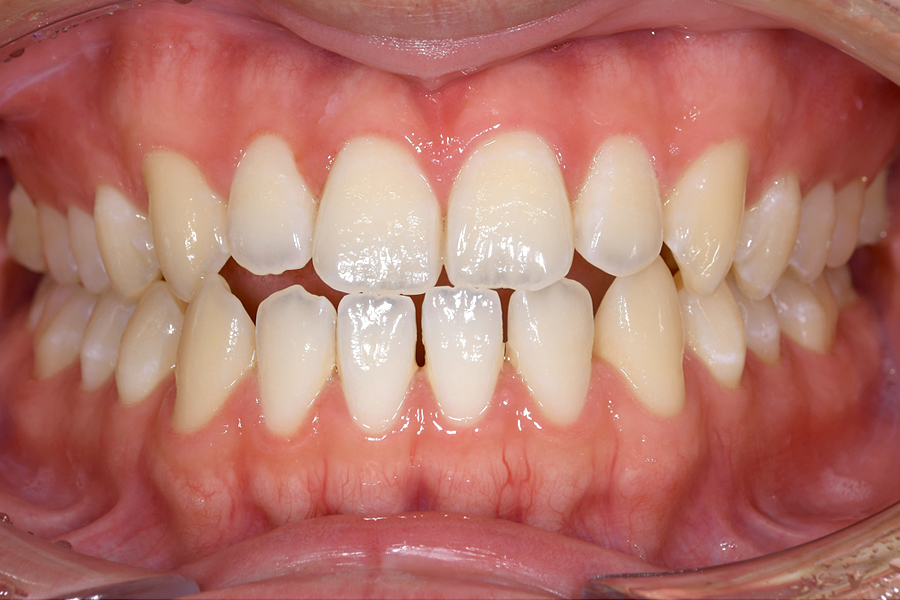

| 主訴 | 見た目を治したい、歯を白くしたい |

|---|---|

| 治療期間 | 1年6か月 |

| 治療費 | マウスピース矯正と ホームホワイトニングセット 1,022,350円(税込) |

| 治療内容 | 目立ちにくいマウスピース矯正 (非抜歯矯正) 歯と歯の間に隙間をつくることにより、歯列弓を広げながら治療を行いました。 また矯正用マウスピースをトレー代わりにし、ジェルを入れてホームホワイトニングを同時に行っております。 |

| 治療のリスク | ・後戻りする可能性があるのでリテーナーを最低でも矯正期間以上はつける必要があります。 ・ホワイトニング後、一時的に痛みが出る場合があります。 |